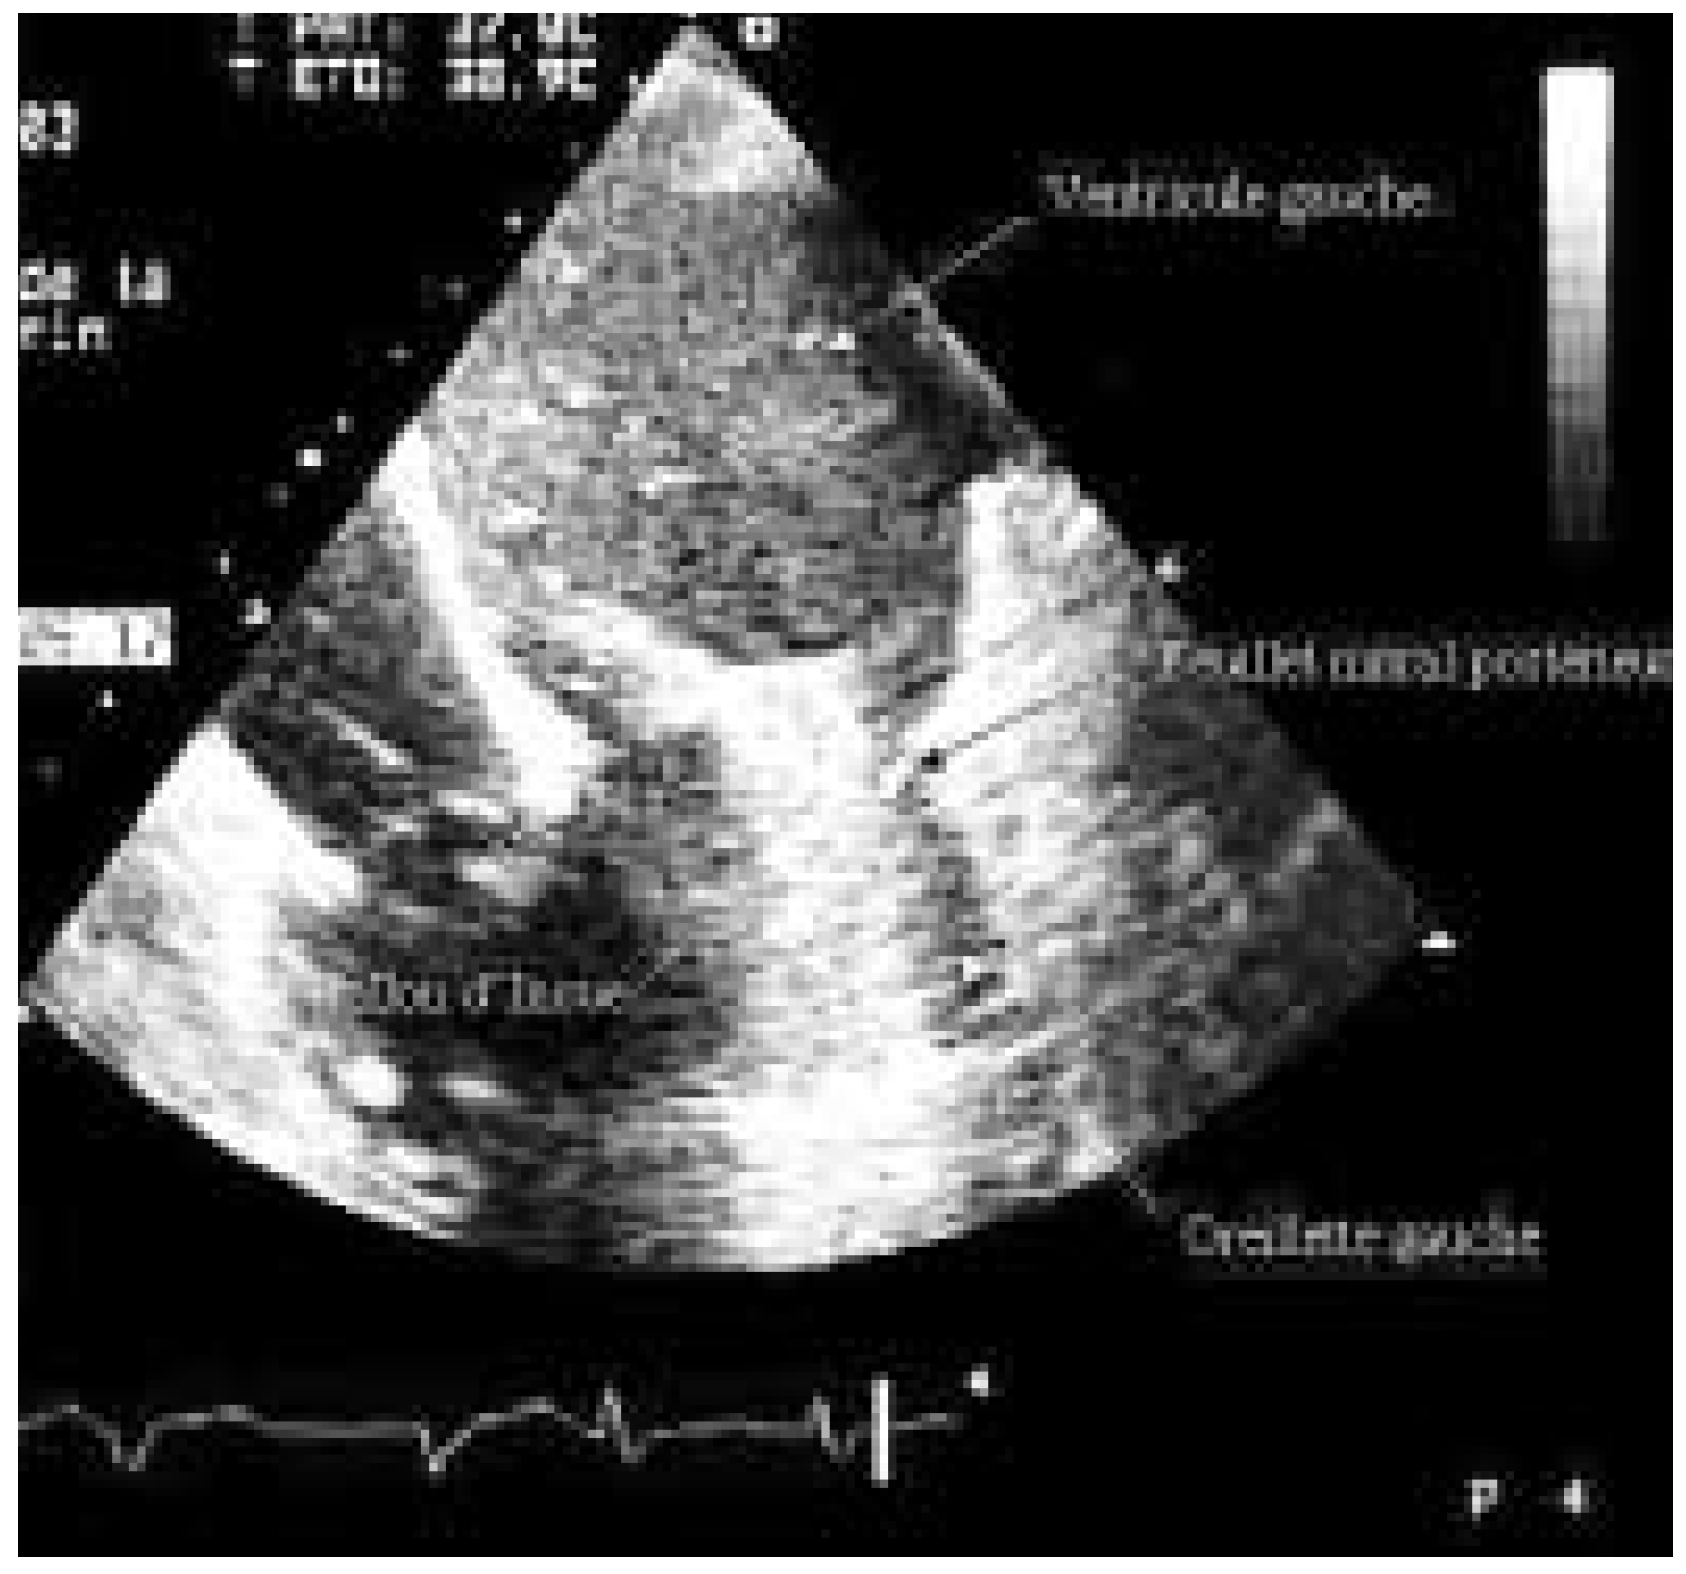

Sténose Mitrale et Valvuloplastie Mitrale Percutanée

Description du cas